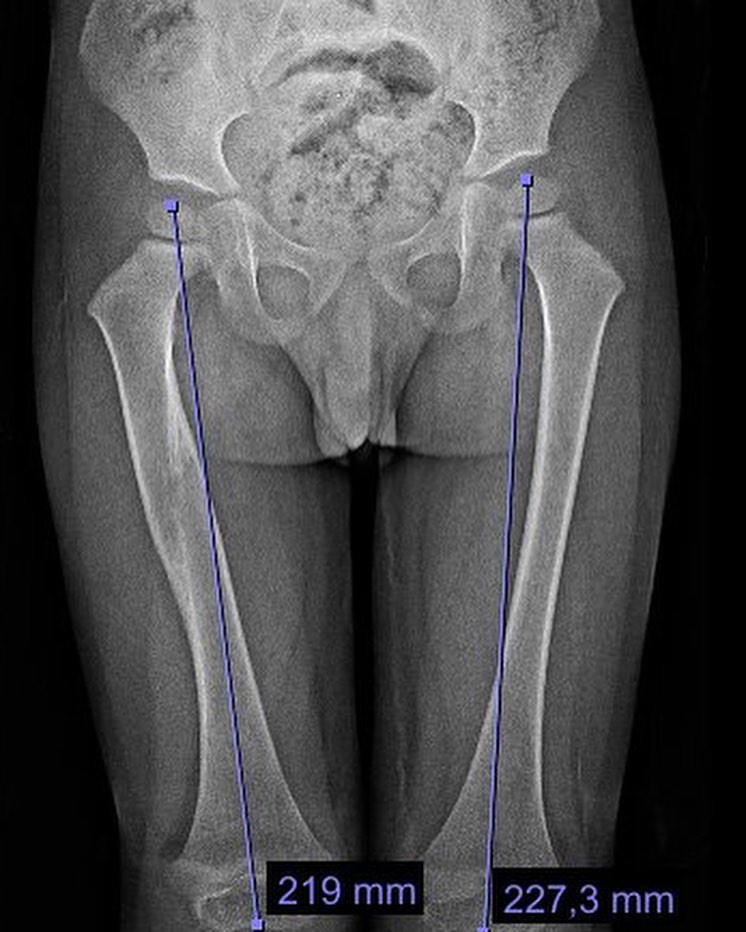

El año pasado mi pacientito Dylan se fracturó el fémur, realizamos tratamiento conservador y ahora está al 💯 Vino a consulta y recibí este delicioso regalo, ¡muchas gracias Dylan!